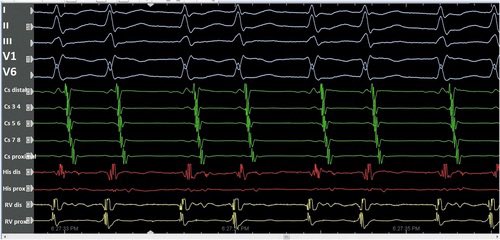

An unstable VT.

Mappable with #StaMP.

Guided by S3 Protocol.